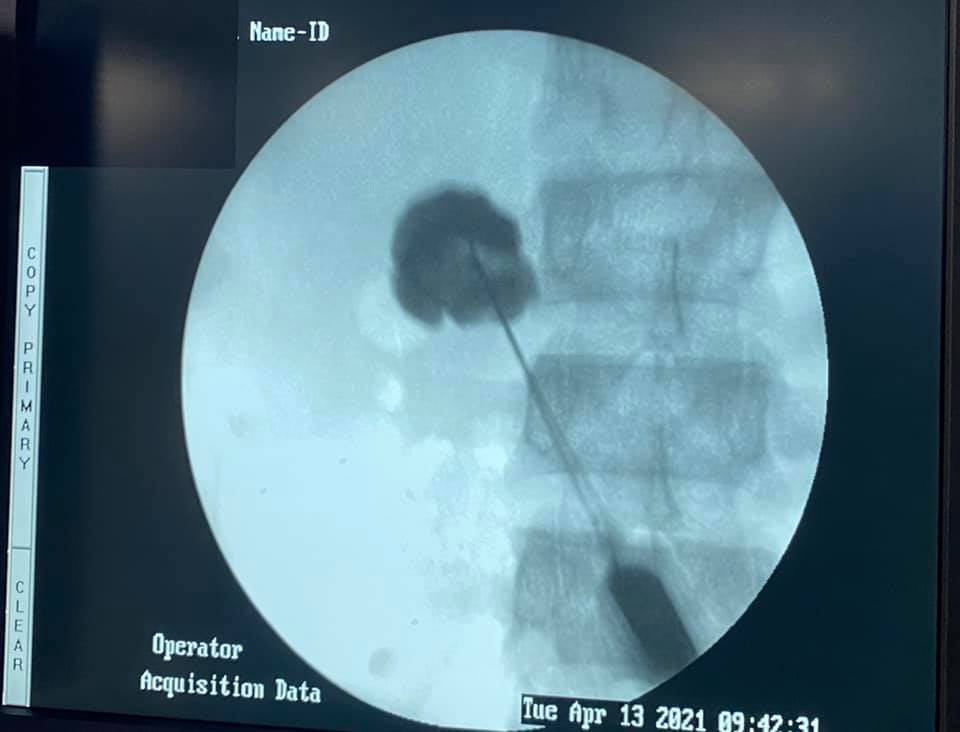

40 year old male with idiopathic chronic pancreatitis presented with intractable pain, sitophobia with severe weight loss (adult male weighs 29 Kg) and history of recurrent episodes of GI bleed. He also has CKD (cr1.7) related to neurogenic bladder. Patient was shifted to us in shock with HB 3 gm % and massive GI bleed. MRI and CT angio showed a large 6x5 cm Pseudoaneurysm in uncinate process of pancreas probably arising from inferior pancreaticoduordenal artery causing hemosuccus pancreas. In view of CKD we chose to tackle aneurysm by direct glue embolisation of aneurysm sac to avoid the high volume contrast of conventional angio (image) Pt was put on NJ feeds in view of severe malnutrition secondary to intractable pain and sitophobia. Post embolisation 2 months later he came back with weight gain of 8 kg and a stable Hb%. His Repeated CT scan showed a persistent intrapancreatic head cyst with dilated pd in body and tail. The aneurysm cavity filled with glue cast has shrunk to almost one fifth the initial size. In view of large duct disease with Pseudoaneurysm we decided to go ahead with a whipple pancreaticoduodenectomy. The post op specimen shows the intrapancreatic cyst and the glue cast of the aneurysm (yellow arrow). His recovery was uneventful and is completely pain free post procedure.